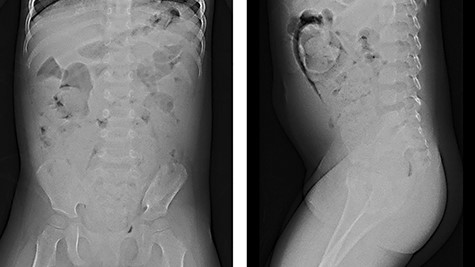

We report herein a case of a 4-year-old girl with ultrashort-segment HD (USHD). She was born at 29 weeks gestation from a twin pregnancy. Her birth weight was 1013 g. After birth, she was administered glycerin enemas to facilitate defecation. Thereafter, she was medicated with sodium picosulfate hydrate for chronic constipation, but she passed stool once in 4–5 days. When she was 4 years old, she was medicated with polyethylene glycol electrolyte solution (MOVICOL® [macrogol 4000]; EA Pharma Co., Ltd, Tokyo, Japan) in another hospital for chronic constipation. After she drank the MOVICOL® twice, her abdomen distended rapidly without passing stool, and she was transported to a hospital. An abdominal X-ray showed a stored stool mass (Fig. 1). A barium enema study revealed dilatation from the rectum to the sigmoid colon due to the stool mass and the rectum was smooth with funnel-shaped tapering toward the anus when she forced herself to defecate (Fig. 2). USHD was suspected, so she underwent anorectal manometry, which showed negative normal reflux. A surgical rectal full-thickness biopsy was performed 2 cm proximal to the dentate line under general anesthesia, which revealed very few ganglion cells in Auerbach’s plexus (Fig. 3a–c). She was suspected to have HD and underwent a Soave endorectal pull-through with an oblique anastomosis, where the pulled-through bowel was anastomosed posteriorly 0.5 cm from the dentate line, laterally 1.0 cm from the dentate line and anteriorly 1.5 cm above this point (Fig. 4). The posterior wall of the aganglionic anorectum was split longitudinally to the level of the dentate line. The resected specimen showed sparse ganglion cells with small cytoplasm in Auerbach’s plexus of the mucosectomy in the rectum (Fig. 5 ①, a and b). In the sigmoid colon of the resected specimen, most of the ganglion cells had scanty cytoplasm, whereas occasional ganglion cells with abundant cytoplasm were visualized (Fig. 5 ②, c and d). She passed stool 4–10 times a day for 6 months postoperatively, but the frequency of passing stool gradually deceased to once or twice a day without anastomotic strictures. Defecation was controlled without medications for 12 months postoperatively.